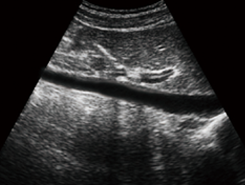

OB&GYN, Urology, Abdomen, Small Parts, Cardiology, Vascular ect.

Product Application

1.OBSTETRIC2.OB3.GYNECOLOGICAL4.UROLOGY5.SMALL ORGAN

6.Cardiac

…